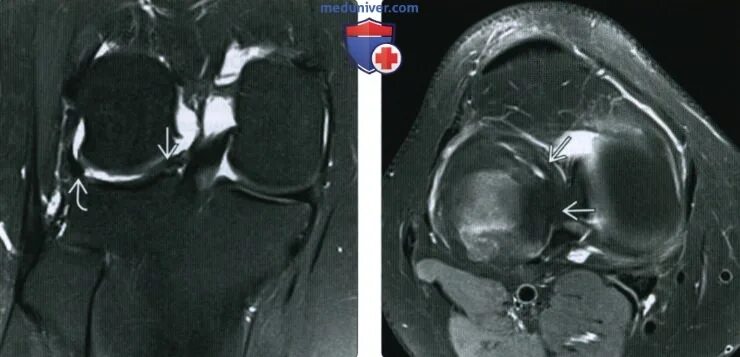

Повреждение мениска мрт